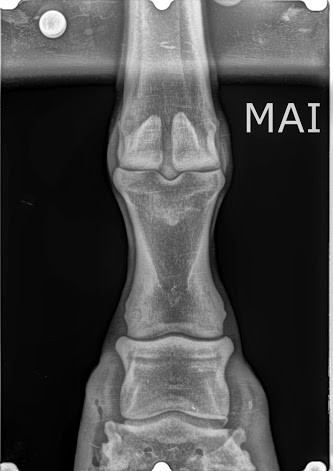

Fractura tibial en un pony

Nos fue remitido a la clínica veterinaria equina un pony con una fractura tibial derecha a consecuencia de una coz que le propinó una yegua. Después de hacer varias radiografías y saber exactamente cuál era el estado de la fractura se procedió a su intervención. Una vez anestesiado, procedimos con la reducción de la fractura […]